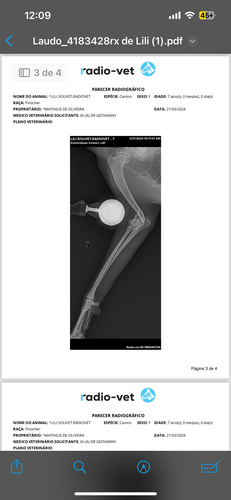

Me chamo Juliana, sou dona da Lili. Lili foi atropelada e quebrou a pata, após os exames descobrimos uma infecção e ela precisou fazer uma piometra, que custou 2024,00. Atualmente Lili está se recuperando da piometra, mas precisa fazer a cirurgia da pata com urgência pois corre risco de fratura exposta. A cirurgia custa 4300,00 e cada dia de internação custa em média 350,00. Gostaria de pedir a ajuda de vocês para que Lili consiga voltar logo para casa! Cada ajuda vai ser bem vinda! Agradeço a todos que puderem ajudar de alguma forma, seja ela oração, divulgação ou financeiro! 🤍